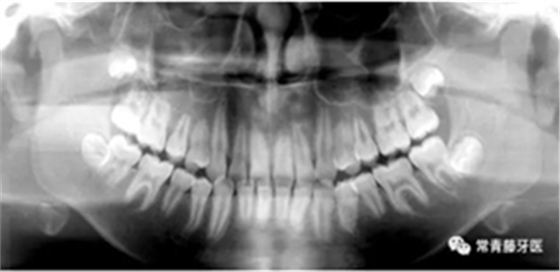

(1)直絲弓矯治器排齊上牙列,配合活動(dòng)腭桿擴(kuò)大上牙弓;

(2)上頜顴牙槽嵴植入種植釘,壓低上后牙,糾正開頜;

(3)拔除38、48,在下頜6、7間植入種植釘,整體遠(yuǎn)移下牙列。

治療過程

6個(gè)月,上牙列擁擠得到解除。上下頜植入種植釘,用于上后牙壓低及下牙列遠(yuǎn)移。

14個(gè)月,前牙開頜得到改善,配合使用垂直牽引。

16個(gè)月,前牙開頜糾正。